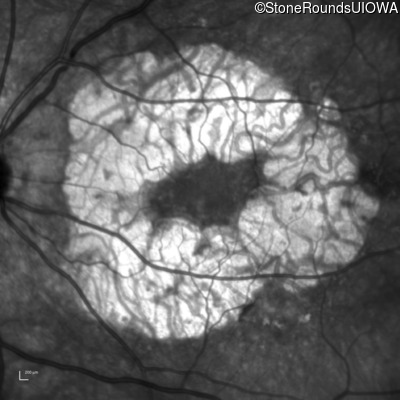

Age at visit: 59 years

This 59 year old woman first experienced defects in her mid peripheral field in the past year. Her hearing worsened in her 30's and she started wearing hearing aids at age 40. She was diagnosed with diabetes at age 39 and began using insulin at age 42.